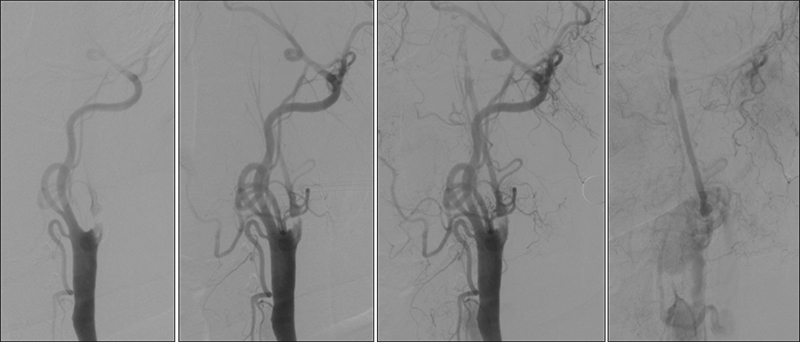

- Γι´ αυτούς τους λόγους σπάνια χρησιμοποιούμε επιθετική αγγειοπλαστική μετά από stenting συμπτωματικών βλαβών. Επίσης πάντα συνηθίζουμε να αναρροφούμε μετά την αγγειοπλαστική από τον οδηγό καθετήρα μέσα από το stent πριν αφαιρέσουμε το φίλτρο.

- Επιλέγουμε άπω προστασία (φίλτρα) σε:

- καλή ανατομία αορτικού τόξου

- χωρίς ενδοαυλικό θρόμβο ή μεγάλου βαθμού στένωση

- όταν η βλάβη εκτείνεται στην κοινή ή/και έξω καρωτίδα, ή υπάρχει απόφραξη της αντίστοιχης καρωτίδος (αντένδειξη γιά εγγύς προστασία)

- Επιλέγουμε εγγύς προστασία (σύστημα MOMA) σε:

- όταν υπάρχει ενδοαυλικός θρόμβος ή σοβαρή στένωση

- ελίκωση της μεταβολβικής έσω καρωτίδος, όταν δεν υπάρχει ζώνη προσγείωσης γιά το φίλτρο (landing zone)

- ιδιαίτερη προσοχή σε απόφραξη της αντίστοιχης καρωτίδος (μειωμένη ανοχή σε αποφρακτικό χρόνο)

- δεν μπορούμε να χρησιμοποιήσουμε ΜΟΜΑ όταν η βλάβη εκτείνεται στην κοινή ή την έξω καρωτίδα.

- Επιλέγουμε διπλή προστασία εγγύς και άπω (σύστημα φίλτρου + MOMA) σε:

- Σε ενδοαυλικό θρόμβο μπορούμε να χρησιμοποιήσουμε και τίς δύο ζώνες ασφαλείας.